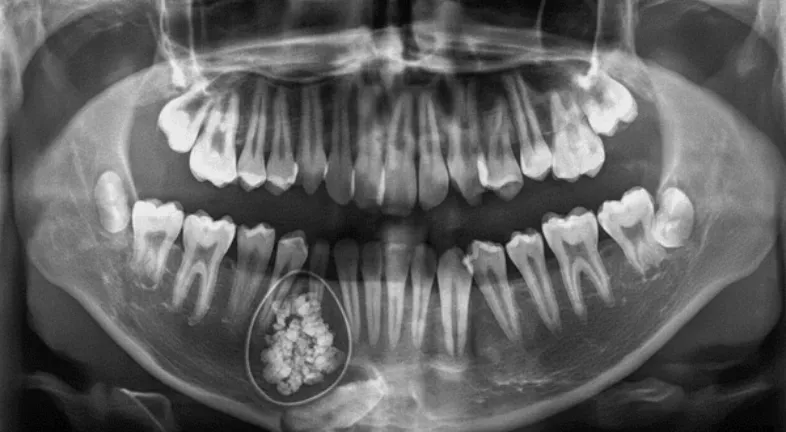

These look like tiny, fully formed teeth. Little “denticles.” Almost adorable, if you forget they’re growing inside your jaw. Compound odontoma teeth clusters usually appear in the anterior (front) section of the upper jaw.

These are more chaotic. A jumbled mass of enamel and dentin that doesn't resemble any recognizable tooth shape. Imagine the building materials of a tooth thrown into a blender. Complex odontomas are typically found in the molar area.

A regular dental X-ray usually reveals the mass. Sometimes, a compound odontoma looks so distinct (with its tooth-like bits) that dentists identify it instantly.